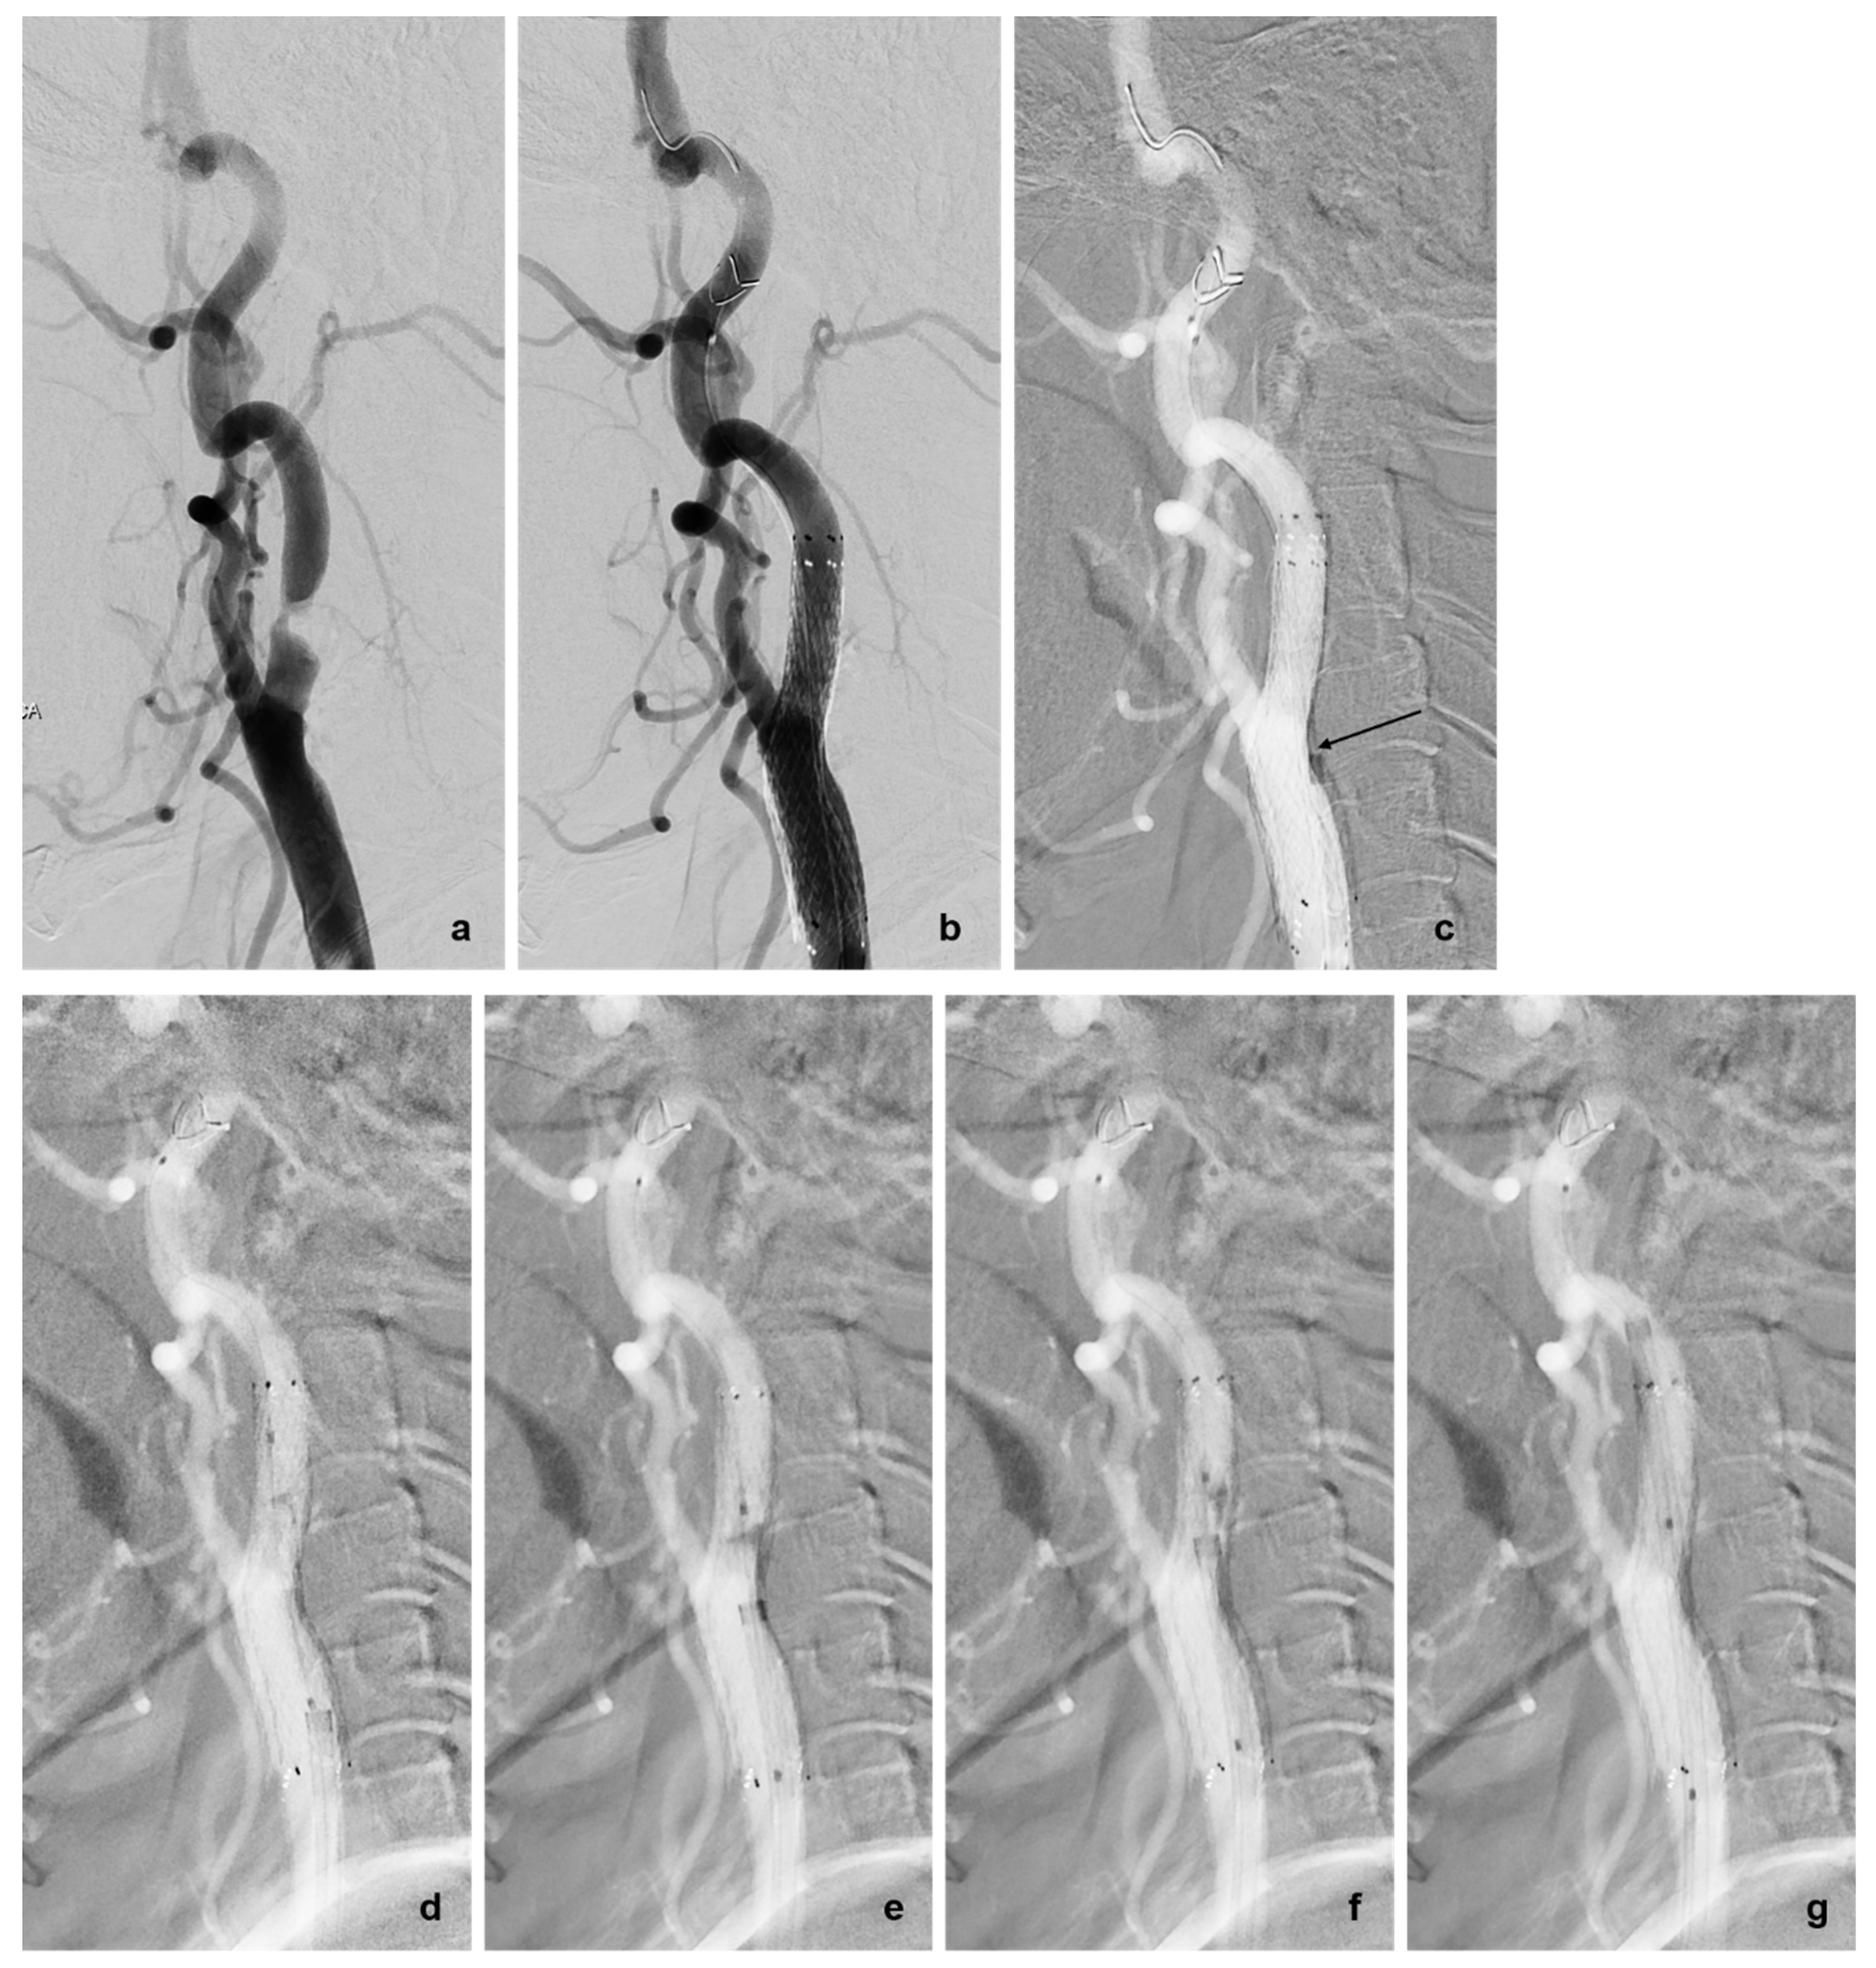

3.2. Rescue Techniques for Adverse Events Related to EPD